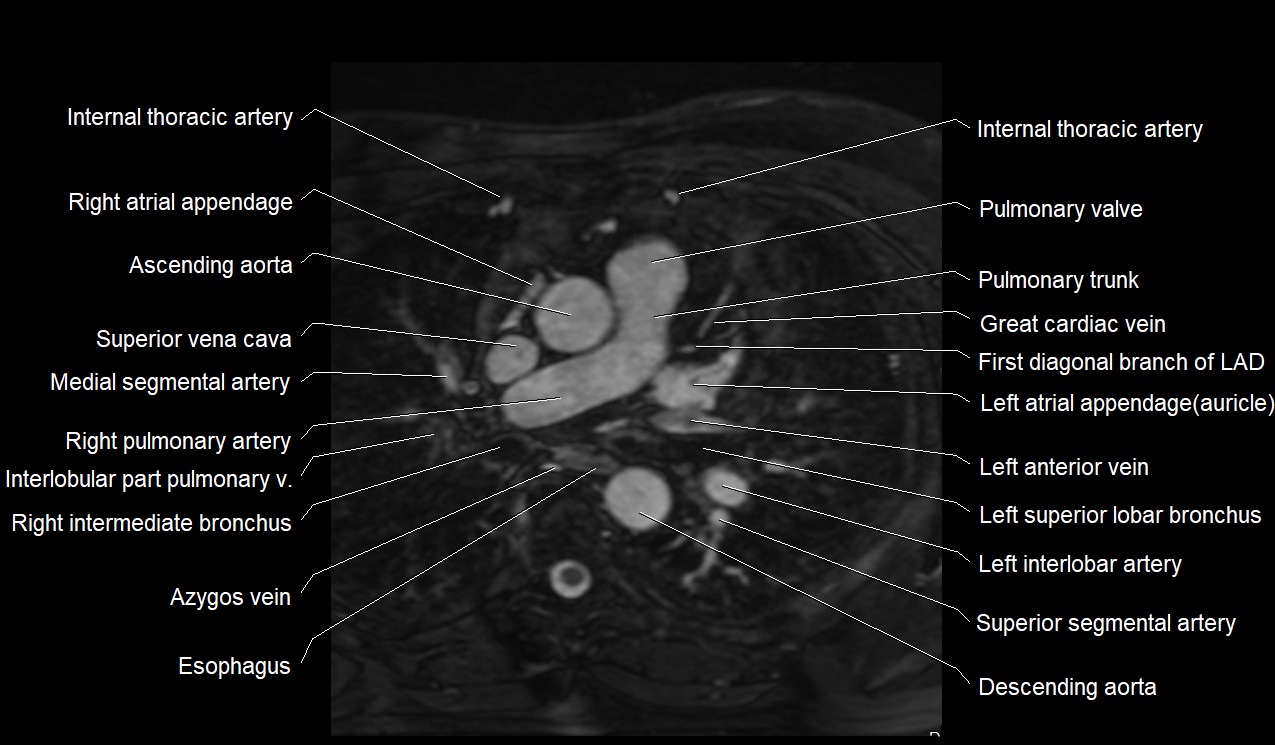

MRI image